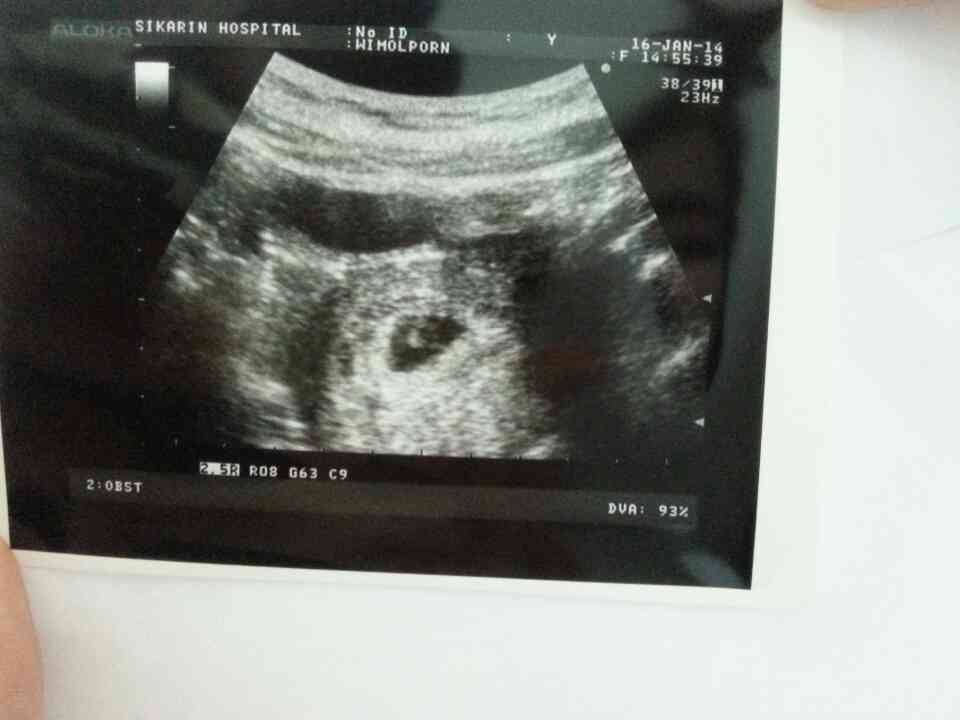

เมื่อวานเพิ่งไปฝากท้องที่รพ.เอกชนคะ หลังจากคุณหมอซักประวัติ ก็ขออัลตร้าซาวน์ดูท้องซะหน่อย

แล้วก็ได้รูปนี้มาคะ ครั้งแรกที่เห็นหัวใจลูกเต้น น้ำตาแทบไหลแต่ขอกลั้นไว้ เพราะอายคุณหมอคะ อิอิ